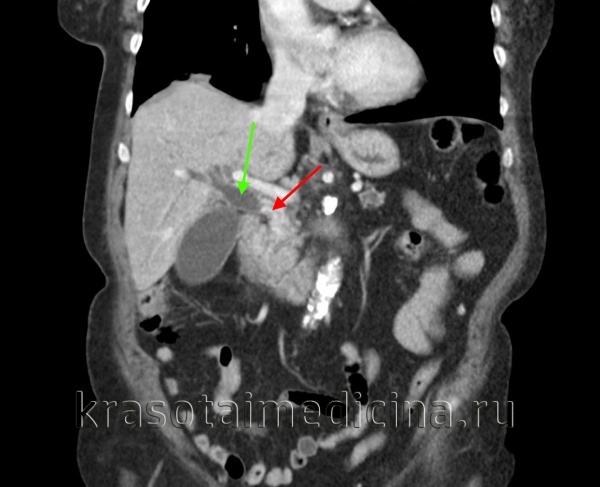

(Левый) У пациентки 67 лет с острым панкреатитом на сагиттальном УЗ срезе определяется крупное полипоидное объемное образование дна желчного пузыря, имеющее собственную сосудистую сеть.

(Правый) При МРТ в просвете желчного пузыря визуализируется дольчатое полипоидное образование, гетерогенное и гиперинтенсивное по сравнению с прилегающей печенью. Обратите внимание на угловатый конкремент в шейке желчного пузыря и отечность поджелудочной железы, вызванную острым интерстициальным отечным панкреатитом.